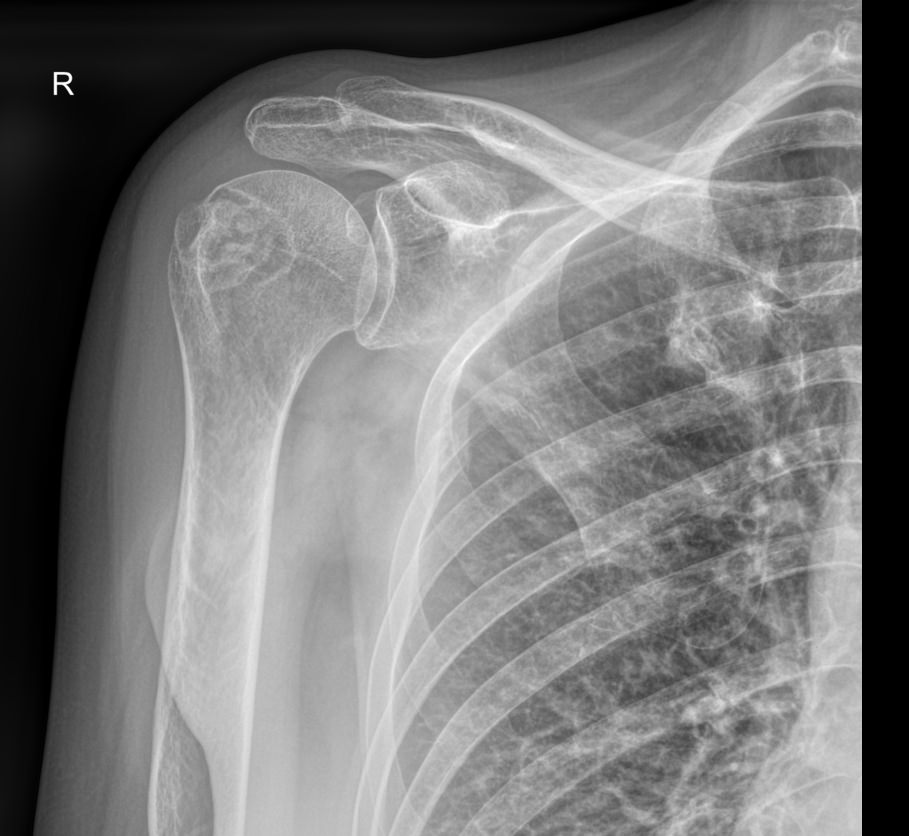

Плечевой сустав ― крупное сочленение, соединяющее верхнюю конечность с телом. По строению он считается простым за счет всего двух суставных поверхностей, для него доступны движения во многих направлениях, что обеспечивает большую свободу для действий рукой. Соответственно, и травма суставу может быть нанесена с разных сторон: при ударе, падении на руку, дергании за нее или резком поднятии большого веса. Кроме вывихов и переломов сустав подвержен системным заболеваниям, типичным для суставов.

Рентгенография относится к стандартным методам диагностики плечевых суставов. На снимке можно обнаружить все патологические изменения, произошедшие в данной области, а также стадии болезни. Рентген используется также для выбора метода лечения и его контроля. Рентгеновское оборудование последнего поколения позволяет делать серию снимков с минимальной дозой облучения. Это важно, так как дает возможность выполнить необходимое количество снимков в динамике.

Снимки выполняются в разных проекциях, в зависимости от того, какой элемент сустава требуется визуализировать.